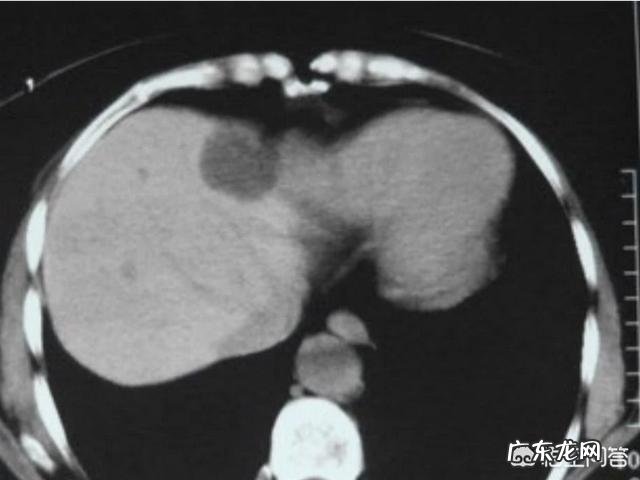

文章插图